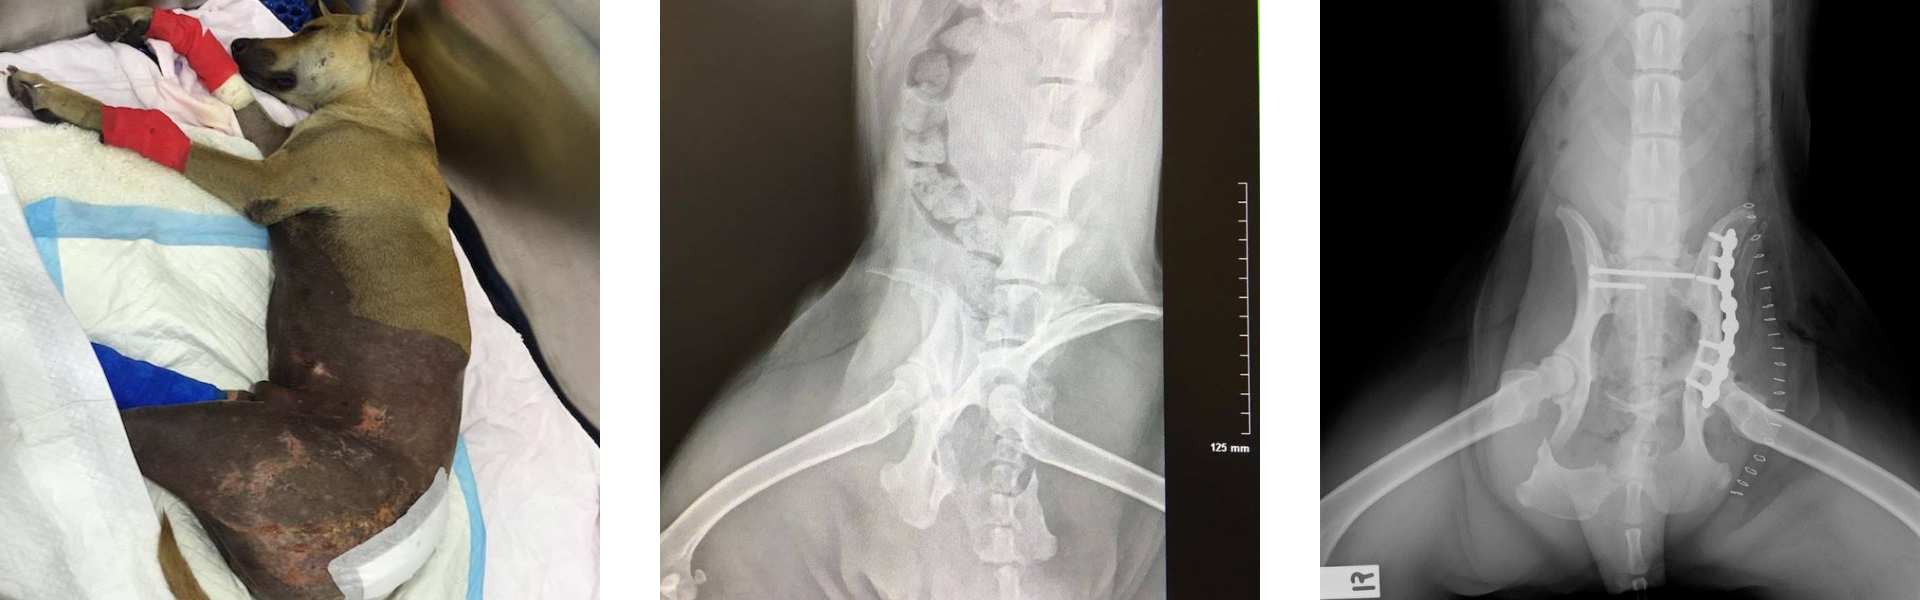

The diagnosis was grim: multiple fractures, a shattered pelvis, and possible spinal damage. Sammy couldn’t stand, couldn’t control his bladder, and his right hind leg was cold and motionless. The odds were against him - but the incredible team of surgeons, nurses, and volunteers believed in his will to survive.

Surgery was a gamble, and one that required significant resources and support. With the help of generous donors and tireless caregivers, Sammy underwent a long and complex operation. He needed blood transfusions and round-the-clock care. After two challenging weeks in hospital, he was finally stable enough to be discharged into foster care.